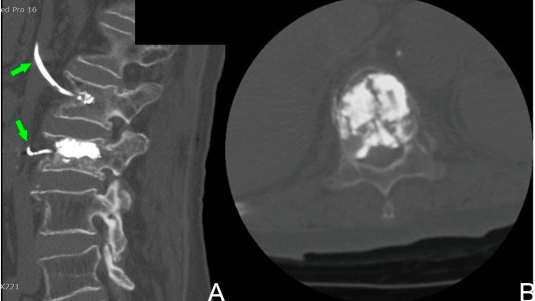

الحقن الإسمنتي البالوني للفقرات هو إجراء جراحي بتداخل محدود يستخدم لعلاج